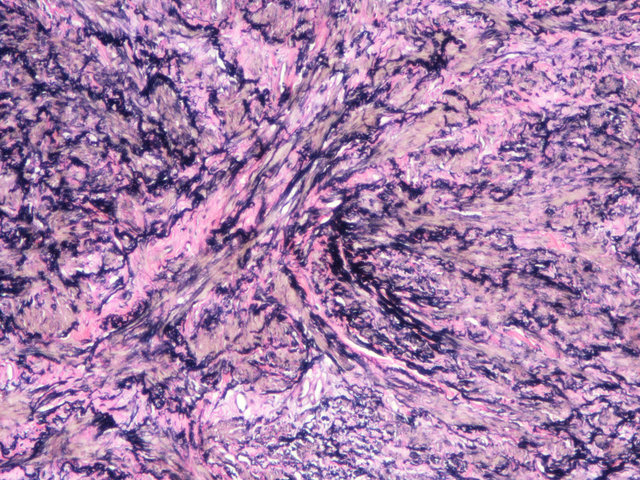

EVG染色样片参考:

弹性纤维呈蓝黑色;胶原纤维呈红色;背景呈淡黄色。

EVG染色方法能显示黑色弹性纤维与红色胶原纤维,一些弹性组织萎缩的肺气肿病例、动脉粥样硬化的弹性纤维变薄和缺失 及其他血管疾病均可使用此方法进行鉴别。